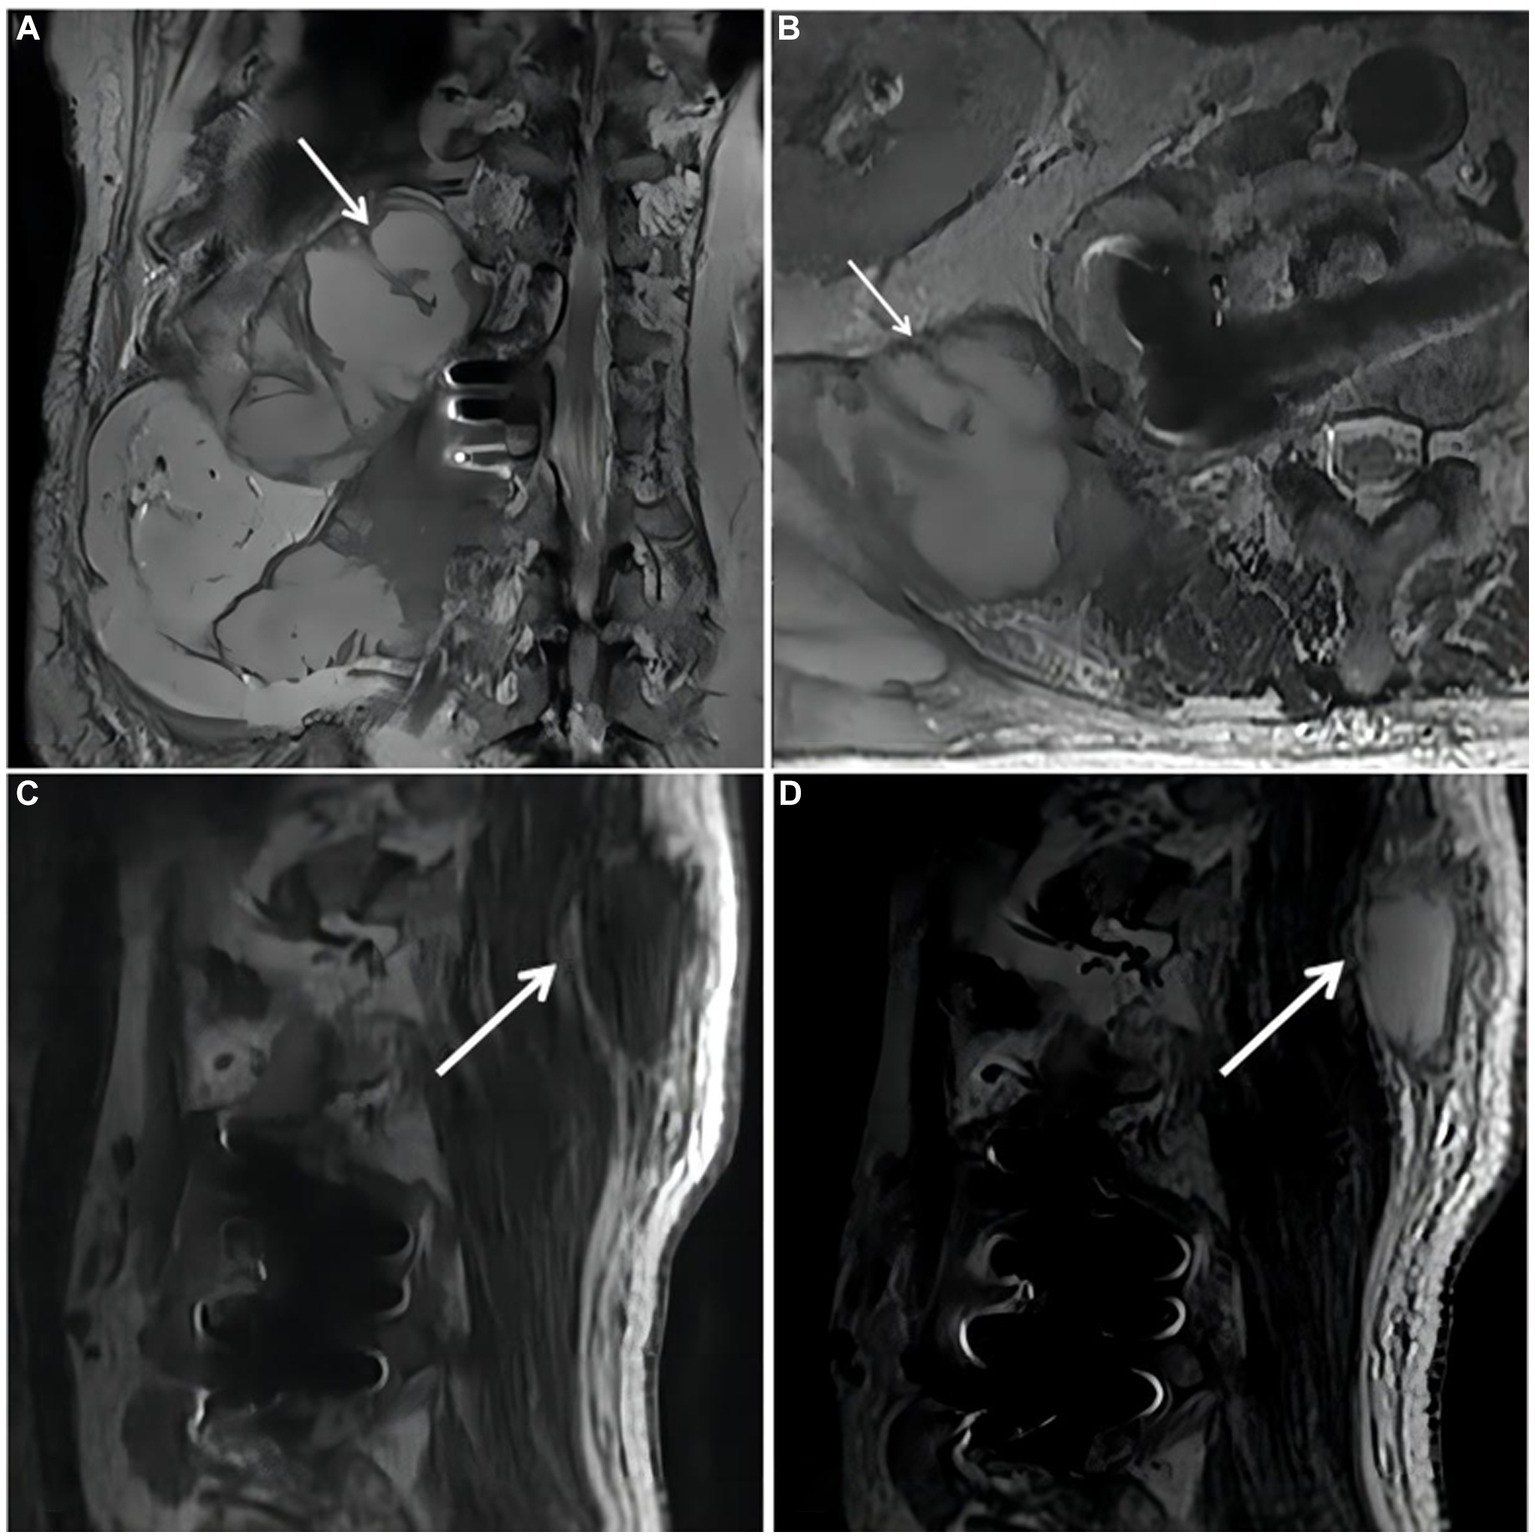

On October 18, 2018,the patient was admitted to our hospital for further evaluation and treatment after 1-week period of anti-tuberculosis treatment. Physical examination revealed tenderness in the thoracolumbar spine, specifically at the level spanning from thoracic vertebra 9 to lumbar vertebra 3. Additionally, a visible mass measuring approximately 20 × 35 cm was detected on the right side of the lumbar region. The test results show a hemoglobin level of 110 g/L, a fasting blood glucose of 8.44 mmol/L, and no abnormalities in liver and kidney function. The results of the infection-related tests are shown in eTable 1. Eight sputum smears were examined for bacteria, fungi, and mycobacteria, and all smears showed no abnormalities. Furthermore, various tests yielded negative results, including urinalysis, stool examination, electrolyte levels, liver and kidney function tests, serologic markers for viral hepatitis, HIV antibody test, fluorescent detection of tuberculosis bacilli DNA, tuberculin skin test, gamma interferon release assay, TORCH-IgM testing (antibody detection for toxoplasmosis, rubella virus, cytomegalovirus [CMV], and herpes simplex virus), Epstein–Barr (EB) virus DNA, CMV DNA, 1,3-β-D-glucan assay, and galactomannan antigen detection assay. An enhanced CT scan of the entire abdomen revealed significant swelling and multiple low-density masses within the right erector spinae, psoas major, and quadratus lumborum muscles. This roughly corresponds to the level between thoracic vertebra 10 and lumbar vertebra 4. The largest mass measured approximately 12.2 × 10.1 cm and displayed mild ring enhancement following CT scan contrast medium injection (contrast medium: iodixanol injection) (Figure 1). Magnetic resonance imaging (MRI) of the thoracolumbar spine revealed multiple irregular nodular and patchy lesions on the right side, spanning from the level between thoracic vertebra 10 and lumbar vertebra 3. These lesions exhibited long T1 and T2 signal intensities and affected the right psoas major, quadratus lumborum, and erector spinae muscles and subcutaneous tissues. The largest lesion measured approximately 12.4 × 9.1 cm (Figure 2).

Figure 2

Magnetic resonance imaging (MRI) of the thoracolumbar spine. (A). Coronal plane of the MRI scan revealed irregular patchy long T2 signal shadows at the right side of thoracolumbar vertebrae (starting from the level of T10). (B). Cross section of the lumbar vertebra MRI scan revealed irregular patchy long T2 signal shadows at the right side (the level of L2). (C,D). Sagittal plane of thoracolumbar spine MRI scan revealed long T1 and long T2 signal shadows, starting from the level of T10 and affecting subcutaneous tissue.